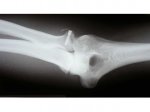

hola

Me gustaria unirme al club de "la cabeza del radio". Yo tengo este tipo de fractura, me cai y crac! un trozo de la cabeza radial se rompio y se desplazo un poquito y me pusieron un tornillin (ver radiografias).La cosa va de la siguiente manera: la pronosupinacion, que era lo que mas me preocupaba va, mas o menos, pero la pessadilla es estirar y flexionar el brazo , que esta resultando lo peor.Me dicen que en principio no deberia costarme tanto ya que el radio no interviene tanto, pero claro ,cuando tienes una fractura no solo se daña el hueso,la capsula que rodea la articulacion, tejido ligamentoso etc tambien.Al traumatologo le falto tiempo para decirme que lo mejor es quitarme la cabeza del radio ( conviene recordar que todas las soluciones que los traumatologos proponen pasan por el quirofano y en cierto modo no pueden hacer otra cosa).YO estuve mirando textos medicos y pone "es solo recomendable en pacientes con poca exigencia de su codo") y yo tengo mucha!!.El fisio dice que el no nota tope oseo, esto es importante porque puede indicar que el movimiento no lo impide el hueso reconstruido sino "otra cosa" con lo que lo de quitar la cabeza no se si solucionaria el problema.Y asi esta la cosa.. me van a quitar la rehabilitacion despues de dos meses y medio y me van a mandar de nuevo al trauma pa que me proponga su operacion..no se que hacer.El fisio dice que no haga nada hasta pasados 6 meses que los tejidos se van elongando y estirare etc. Yo sigo vuestras evoluciones y pondre las mias aqui ,porque cuando las compartes con alguien te agobias menos..salud y suerte a todos[/img]

Adjuntos: